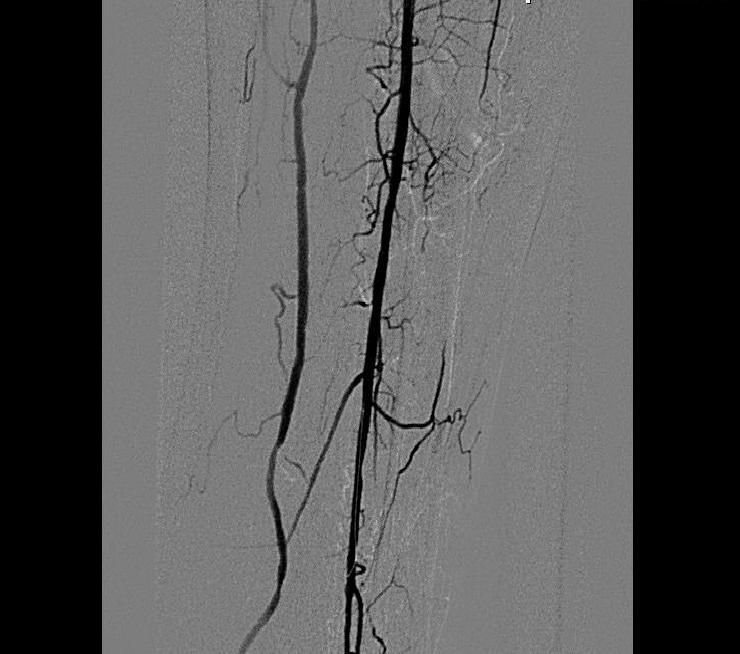

B зону остаточного стеноза в средней трети МБА установлен стент Cypher